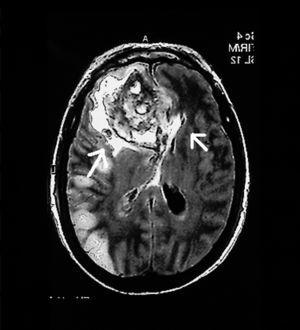

Mujer de 65 años, que ingresó en el Servicio de Medicina Intensiva diagnosticada de meningitis por Streptococcus pyogenes secundaria a otitis supurada y mastoiditis izquierda. Antibioticoterapia según antibiograma. Se realizó tomografía axial computarizada (TAC) por deterioro del nivel de conciencia compatible con meningitis. Tres días después presentó status convulsivo que fue tratado con inducción de coma barbitúrico; se realizó nueva TAC (fig. 1) sugerente de encefalitis necrotizante corticosubcortical temporooccipital izquierda secundaria a vasculitis o a trombosis venosa cortical. El octavo día de ingreso presentó anisocoria, por lo que se le realizó resonancia magnética (RM) (fig. 2) que demostró hematoma frontal izquierdo espontáneo que requirió drenaje quirúrgico. La enferma estaba recibiendo 80 mg/24 h de heparina sódica en perfusión continua por HDFVVC, con tiempos de cefalina en el rango normal. La paciente presentó mala evolución, falleciendo a los 20 días del ingreso tras limitación del esfuerzo terapéutico en el contexto de shock séptico refractario (cultivos necrópsicos en Pseudomonas aeruginosa en pulmón y serosa pleural) y fallo multiorgánico.

Diagnóstico: meningoencefalitis necrotizante secundaria a mastoiditis por S. pyogenes.